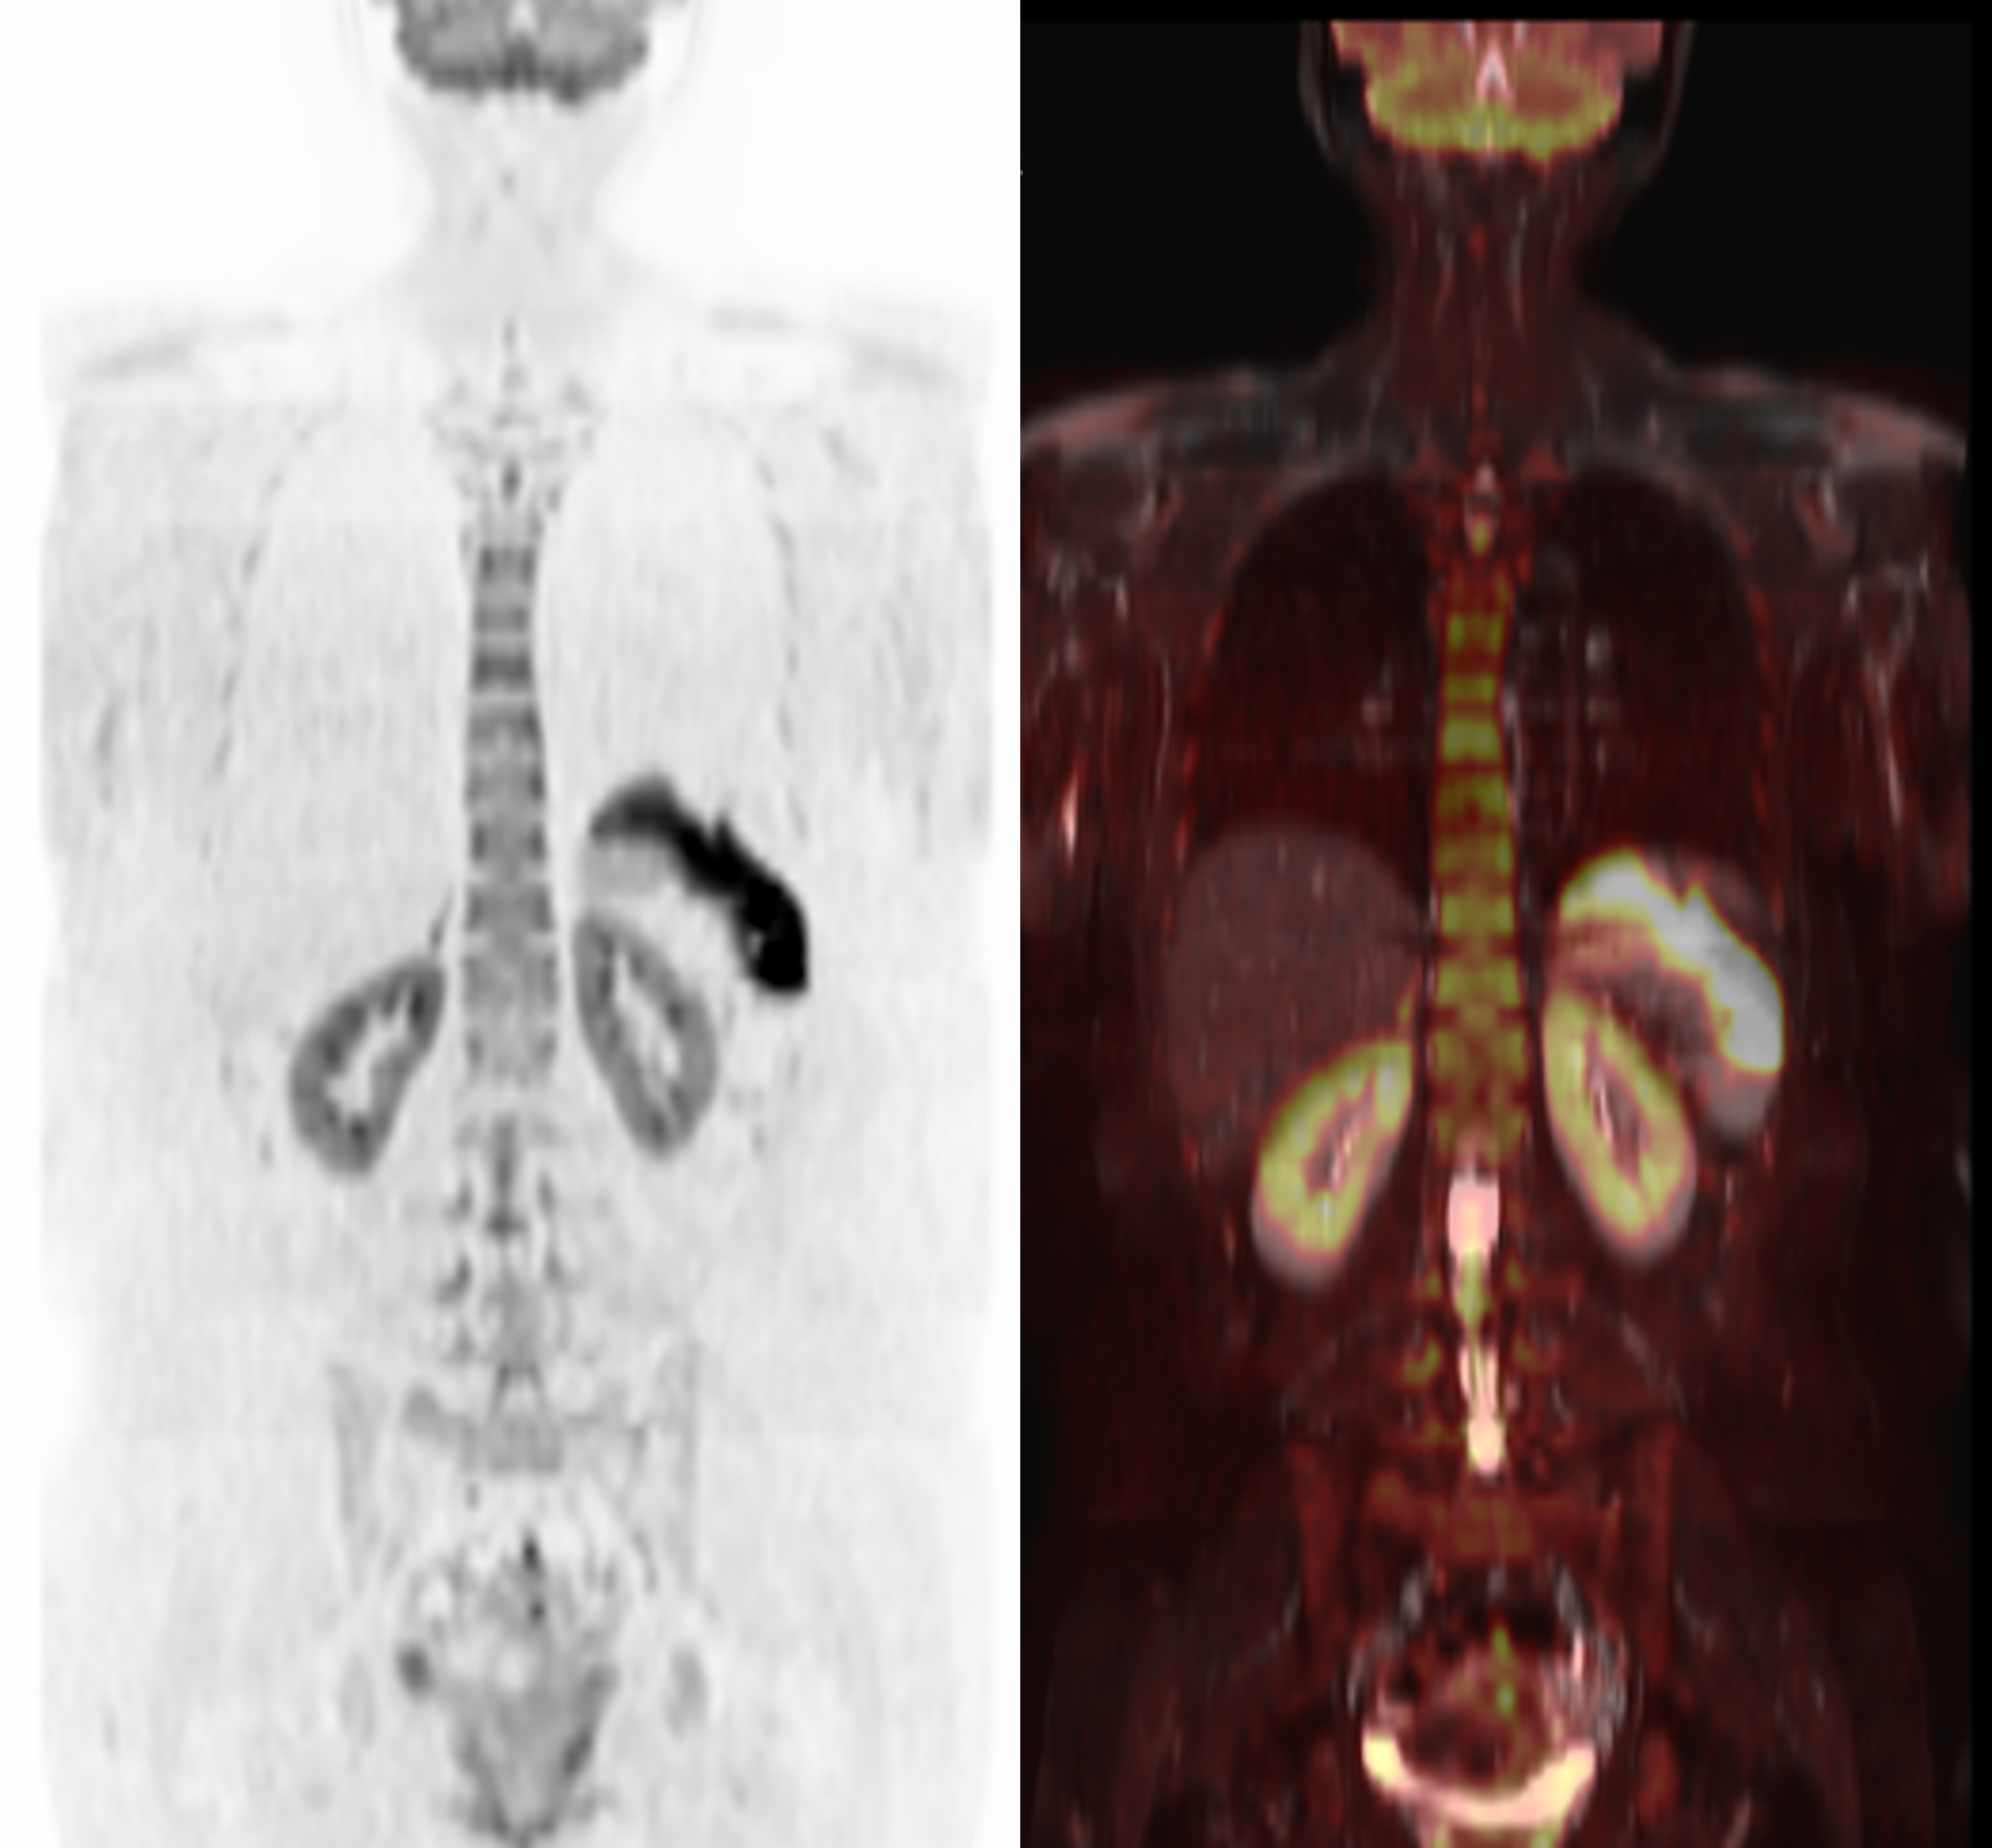

DWIBSとは、2004年に開発された新しい検査方法です。悪性腫瘍の細胞密度が高いことを利用して、細胞間の水の動きを捉え、頸部から骨盤まで一度の検査で悪性腫瘍を検出します。全身のがんを検索する検査としてはPET-CTが広く知られていますが、DWIBSはPET-CTとは異なり 放射性薬剤の投与や被ばくがありません。短時間 寝ているだけで全身のがん検索ができます。DWIBSでは正常組織や炎症などでも「異常」として検出することがあります。そのため、当院ではCT画像とDWIBS画像を比較することで、より信頼度の高い検査結果をご提供しています。DWIBSの苦手とする胃や肺、心臓周囲の病変検出が可能となり、逆にDWIBSで検出された「異常」が偽陽性かどうかの確認もできます。

●MRI(DWIBS)+CT(胸腹部~骨盤)+採血(腫瘍マーカー8項目+一般項目(アミラーゼ・トリプシン・HbA1c・肝機能・血液一般+感染症)

60分程度

検査日から2~3週間後を目安に郵送いたします。

医師による検査結果をご希望の場合は、後日受診してください。(保険診療)

※当日結果説明不可※